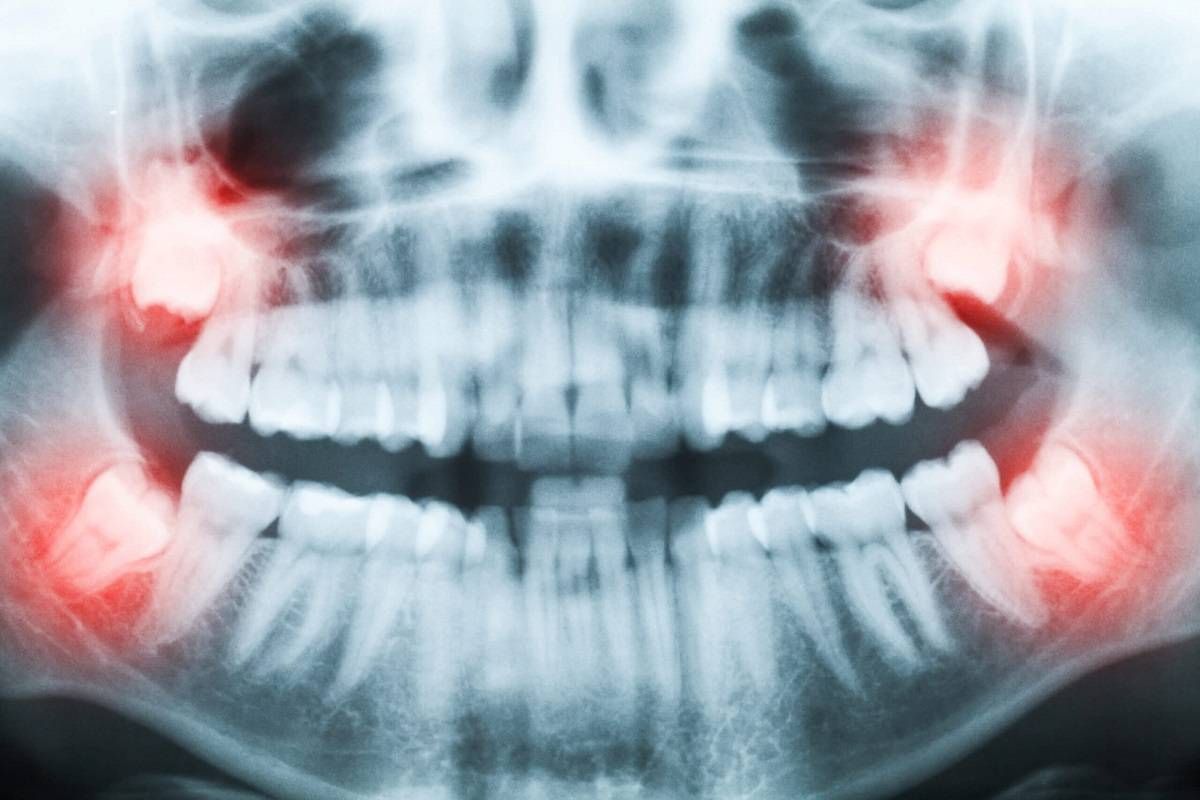

چرا دندان‌های عقل این‌قدر دیر درمی‌آیند؟

دندان‌های عقل بسیار دیر می‌رویند، اما علت این موضوع چیست و آیا این دندان‌ها هرگز برای انسان‌ها مفید بوده است؟